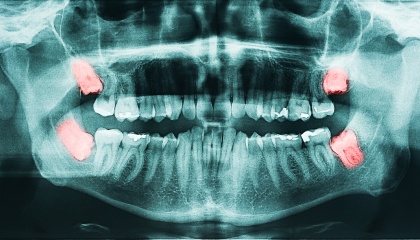

During your initial visit, we’ll thoroughly review your medical history and discuss the wisdom teeth removal process in detail. We’ll take x-rays to assess your teeth and create a personalized treatment plan tailored to your specific needs. This plan will outline the cost, timeline, and steps involved in the procedure. We encourage you to ask any questions you may have to ensure you feel informed and comfortable with the process.